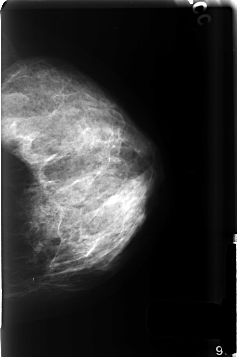

C_0501_1.RIGHT_CC

FILE: C_0501_1.RIGHT_CC.OVERLAY

TOTAL_ABNORMALITIES 1

ABNORMALITY 1

LESION_TYPE CALCIFICATION TYPE DYSTROPHIC DISTRIBUTION CLUSTERED

ASSESSMENT 3

SUBTLETY 5

PATHOLOGY BENIGN

TOTAL_OUTLINES 1

BOUNDARY